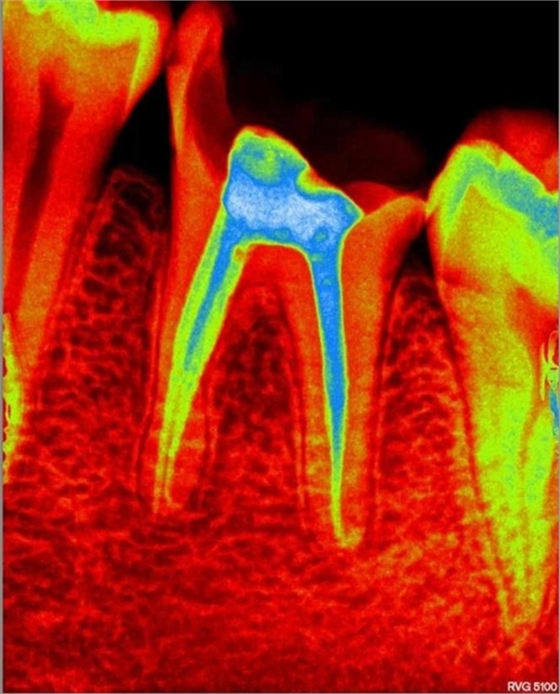

部分病例: